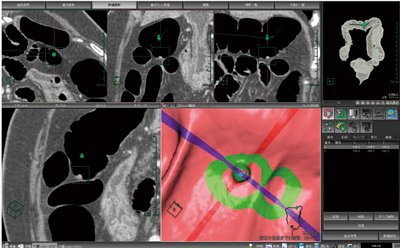

随時,どちらの読影法においても,必要に応じて三次元画像と二次元画像の切り替えを素早く行えることは臨床上重要である(図2)。当社の大腸解析には,仮想内視鏡,開き画像,竹割り画像,カット断面などの3D表示と,MPRだけでなく,自由に断面を回転表示できるオブリークの2D表示との各種表示機能を用意している(図3)。さらに,これらすべての画像上で任意の位置を指定すると,全画像上で位置がリンクして表示されるようになっている(図4)。これは,3Dプライマリー読影法,2Dプライマリー読影法,どちらで行う場合にも非常に重要な機能となる。また,2D表示と3D表示の切り替えを迅速に行うことが可能で,ストレスなく観察を行うことが可能となっている。

図4 3Dプライマリー表示